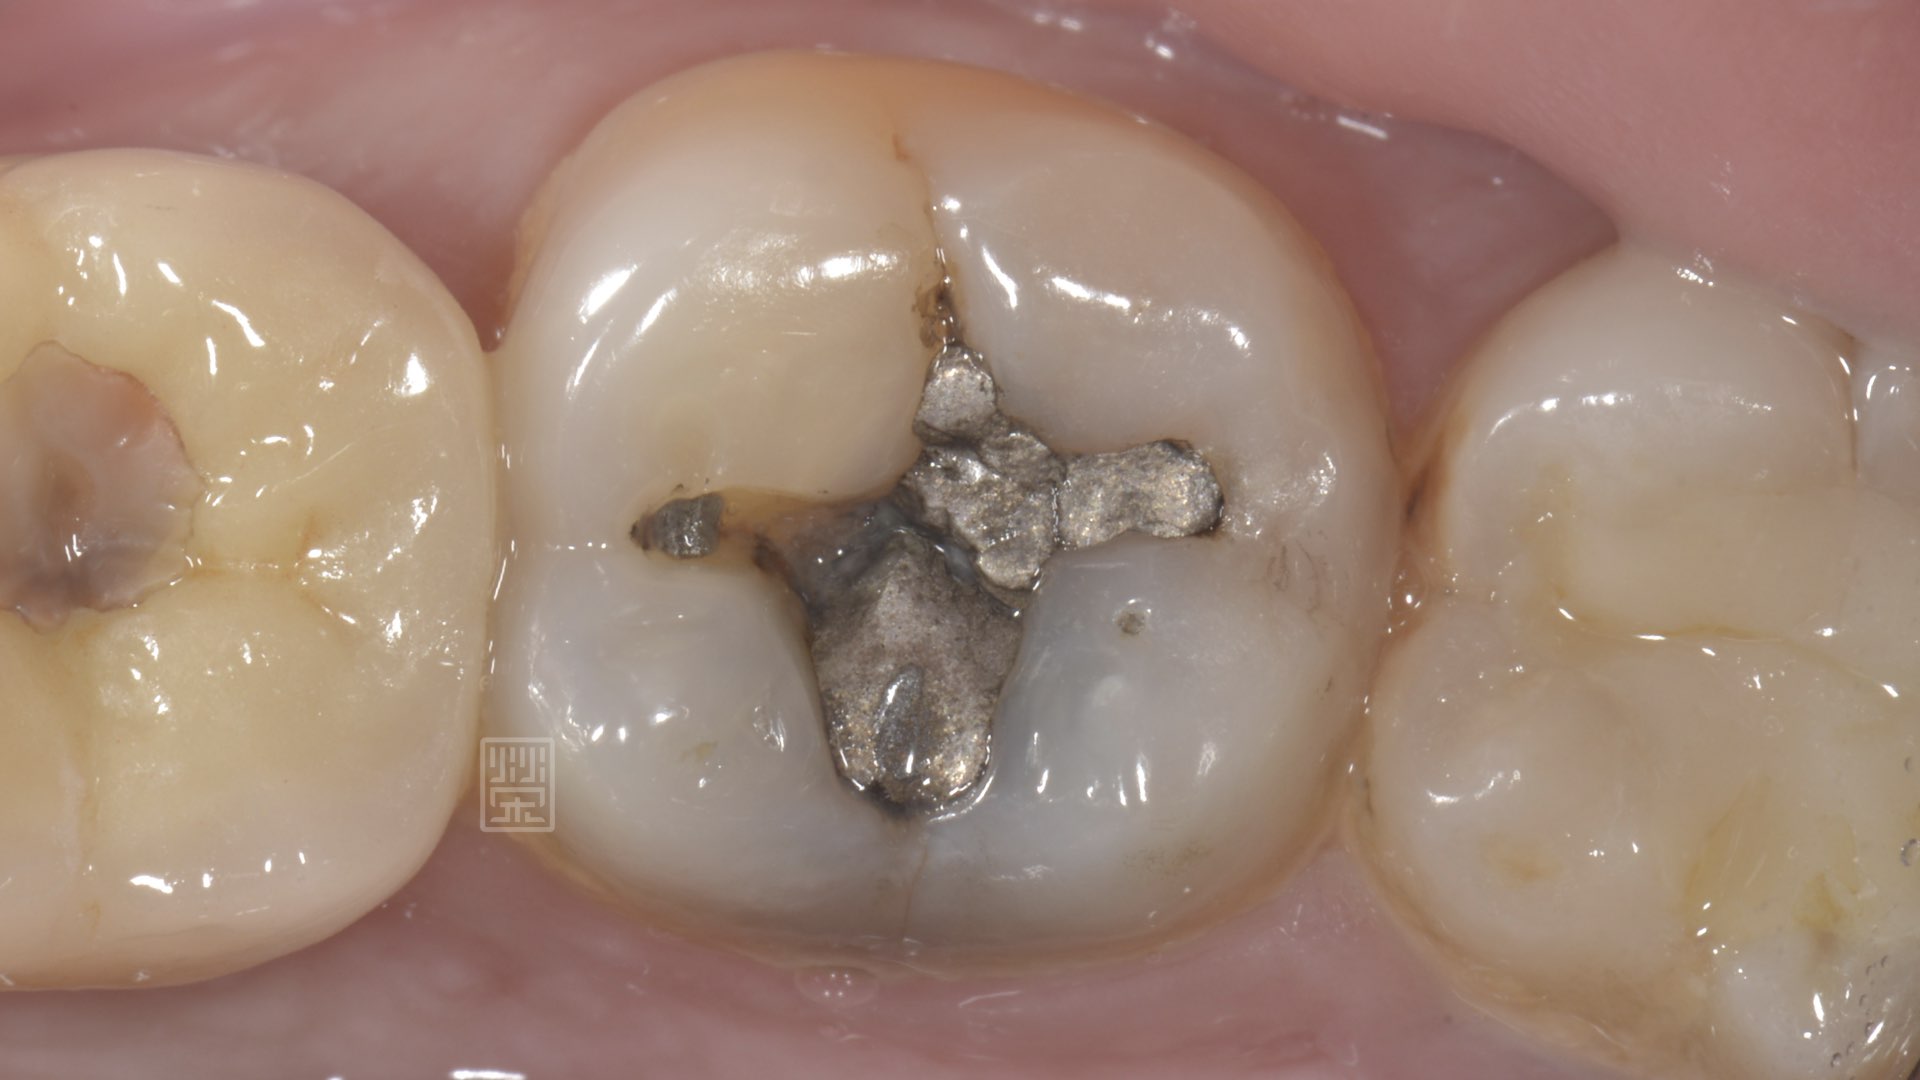

銀粉破裂